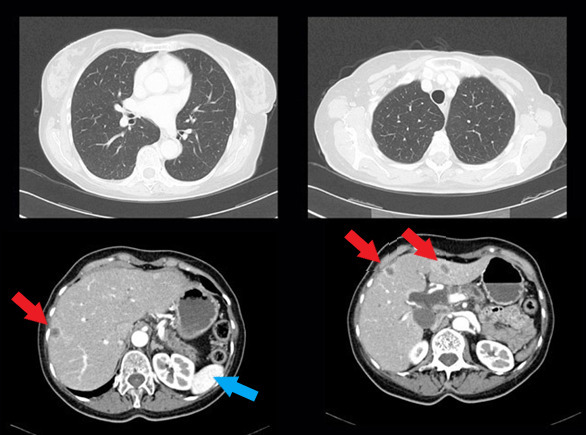

Vous recevez les résultats du scanner demandé (ci-dessous) ; les coupes sont représentatives et suffisent à conclure pour les organes explorés.

Question 9 - Sur cet examen, vous notez (une ou plusieurs réponses exactes) :

Le parenchyme pulmonaire est normal, on distingue uniquement les structures bronchovasculaires habituelles. En revanche on note des lésions hypodenses avec une prise de contraste périphérique hépatiques (flèches rouges) évoquant des lésions secondaires. Le reste du scanner est normal, la rate est visible (flèche bleue).

Le compte rendu du scanner confirme la présence de lésions secondaires hépatiques.